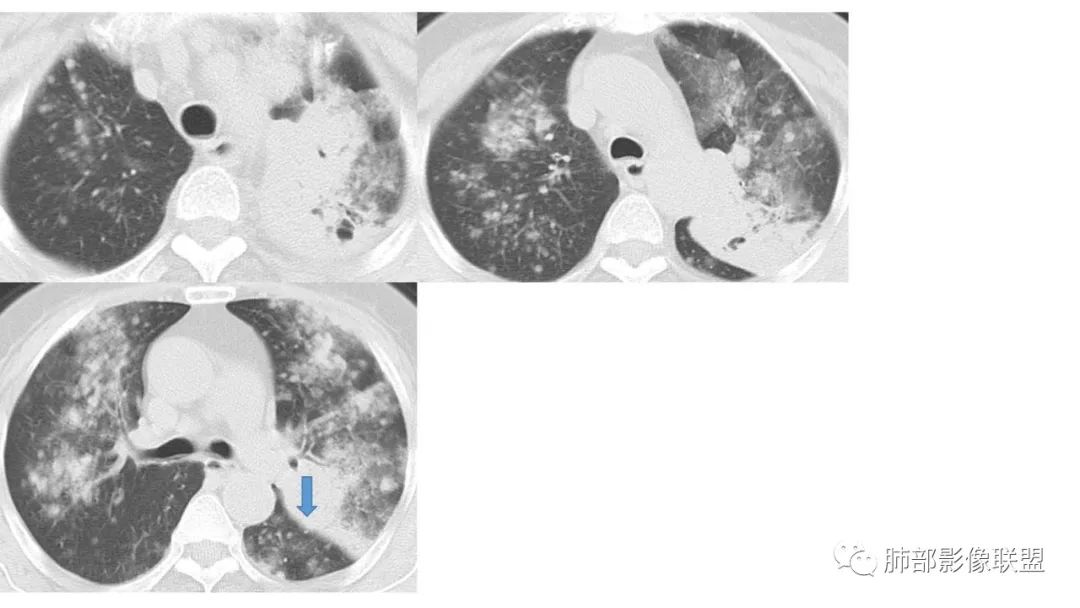

2、病灶常有一个主病灶,常位于下肺。后沿气道播散为多发病灶。

8、斑片常伴有结节,边缘清楚GGO或欠清楚。

9.粘液腺癌的变化规律:结节缓慢发展而来,向周围播散形成斑片后可快速进展,有时支气管镜后或粘液排出后局部可形成好转的假象。病灶可沿肺泡和支气管播散。

4.回到本例,左下肺病变两次好转,均未经过肿瘤治疗,第一次是支气管镜后,第二次是当其他病变都在进展的情况下,左下肺病变范围反而缩小趋于浅淡。